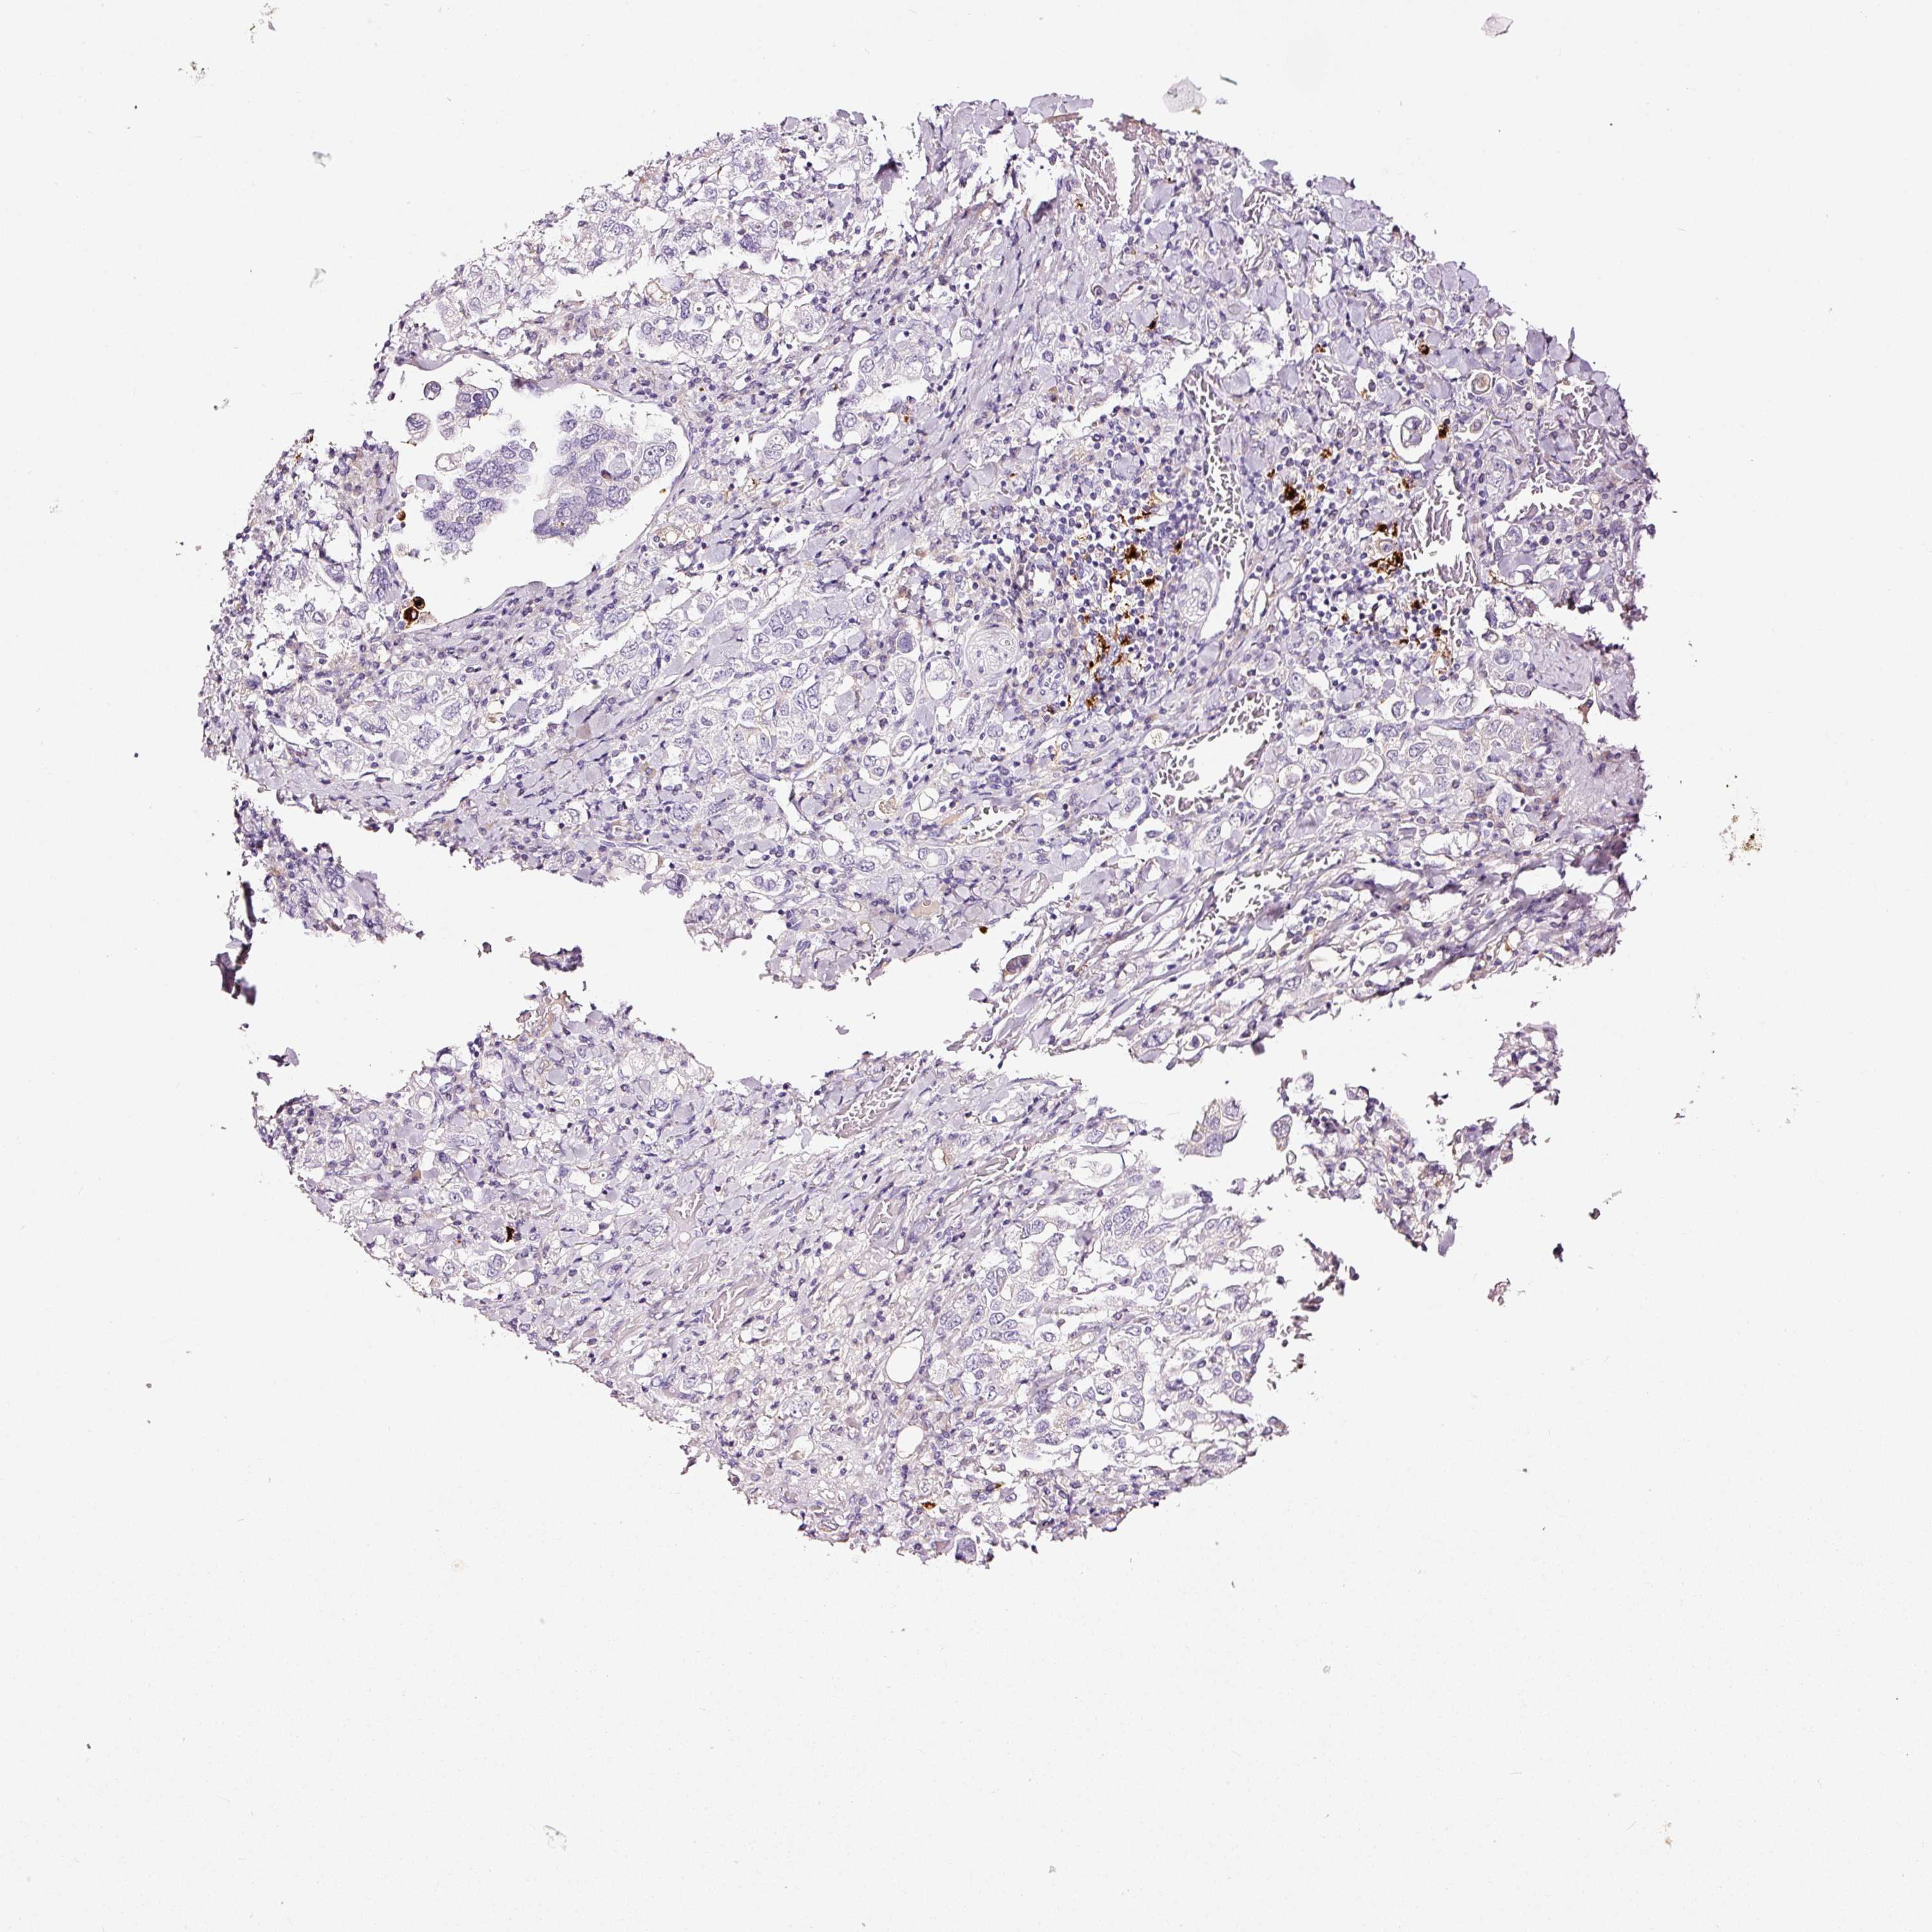

STOMACH CANCER - Protein expressioni

A mouse-over function shows sample information and annotation data. Click on an image to view it in a full screen mode. Samples can be filtered based on level of antibody staining by selecting one or several of the following categories: high, medium, low and not detected. The assay and annotation is described here.

Antibody stainingi

Antibody staining in the annotated cell types in the current human tissue is reported as not detected, low, medium, or high, based on conventional immunohistochemistry profiling in selected tissues. This score is based on the combination of the staining intensity and fraction of stained cells.

Each image is clickable and will lead to virtual microscopy that enables deeper exploration of all samples and also displays staining intensity scores, fraction scores and subcellular localization as well as patient and tissue information for each sample.

Adenocarcinoma, NOS